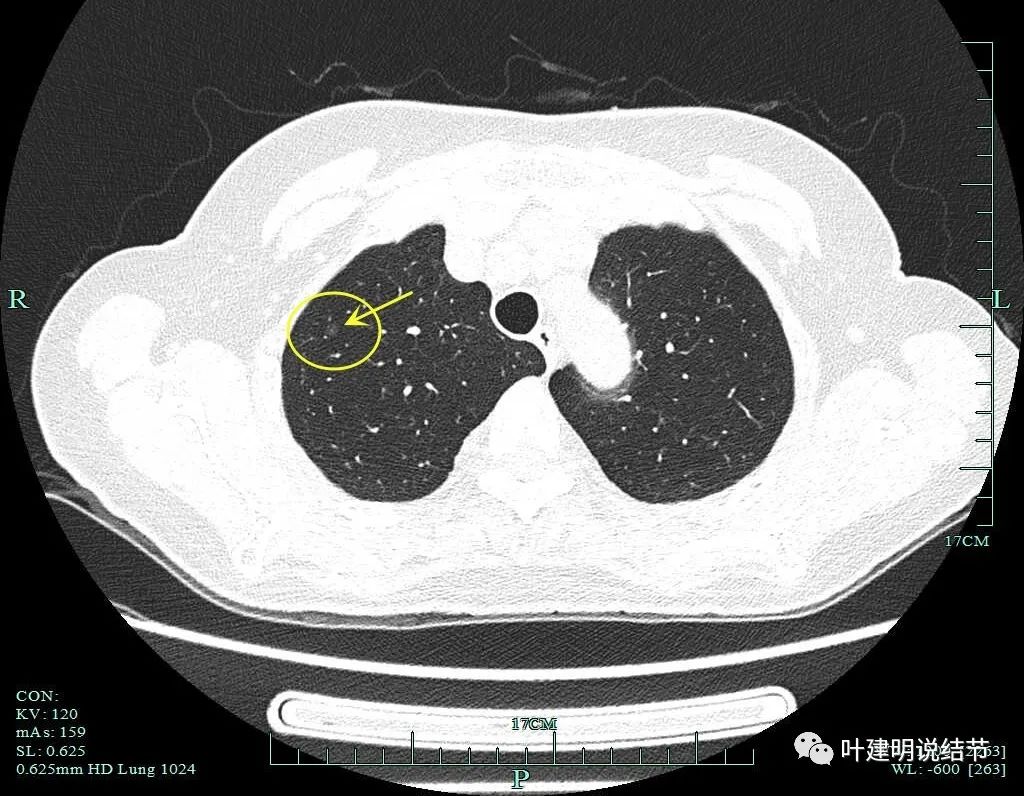

病灶1:右肺尖淡磨玻璃结节,微小而轮廓较清,考虑肺泡上皮增生可能性大,风险低,能随访。

病灶2:右肺尖淡磨玻璃结节,有微小血管进入,轮廓与瘤肺边界清,从密度看不典型增生可能性大,但因有微血管,升一级考虑,所以有原位癌可能性,近期风险不高,可随访。

病灶3:右肺上叶尖段微小磨玻璃结节,约2毫米,在病灶2附近,考虑肺泡上皮增生可能性大,风险低,能随访。

病灶4:右上叶淡磨玻璃结节,轮廓清,没有实性成分,考虑肺泡上皮增生可能性大。风险低,能随访。

病灶5:右上叶前段淡磨玻璃结节,密度低,轮廓清,边缘毛糙,考虑不典型增生可能性较大,风险不算大,能随访。

病灶6:右上叶后段混合磨玻璃结节,实性成分少,总体密度不高,但轮廓清,有血管进入。单凭密度应该原位癌或不典型增生,但因血管征存在升一级考虑,微浸润性腺癌不能除外。有一定风险性,可考虑干预切除或4-6个月复查随访。

病灶7:右肺靠心缘侧微小纯磨玻璃结节,考虑肺泡上皮增生可能性大些,风险低,能随访。